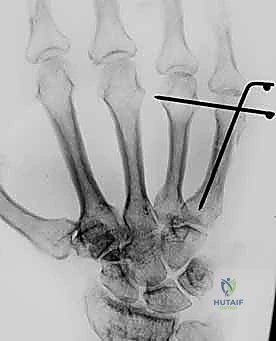

خطوات التثبيت الجراحي - توثيق بصري (Intraoperative Imaging)

يحرص الدكتور هطيف على توثيق خطوات العمل الجراحي لضمان أعلى مستويات الدقة. نستعرض هنا مجموعة من الصور من داخل غرفة العمليات توضح مدى تعقيد ودقة هذه الجراحات:

تتطلب الجراحة انتباهاً خاصاً للأوتار الباسطة والقابضة والأعصاب الدقيقة المحيطة بالعظام. استخدام تقنيات الجراحة الميكروسكوبية (Microsurgery) يضمن عدم الإضرار بهذه الأنسجة الحساسة.